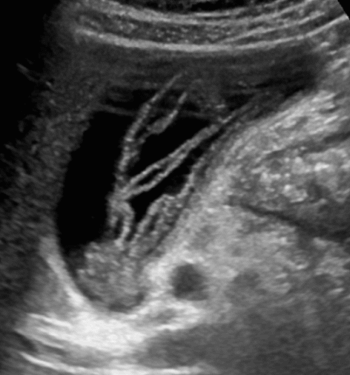

간디스토마증 (Clonorchiasis = Clonorchis Sinensis ) 2. 회충증 (Ascariasis)

- 회충이 소장에서 담도로 기어 올라와 발생

- 폐쇄성 황달, 담관염을 일으킨다